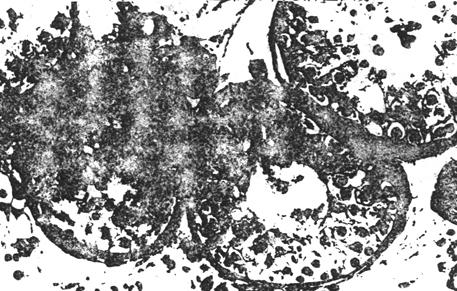

②生精功能低下:曲细精管尚有各级生精细胞,但其数量和层次均有不同程度的减少,细胞排列紊乱。依病变的程度可分为轻、中、重度。轻度约有45%曲细精管病变,但精原细胞基本正常;中度约45~75%以上曲细精管病变,精原细胞缺如基底膜纤维增生少数有透明样变;重度病变很难恢复生育能力。

图8-3-4 生精功能低下,曲细精管生精细胞层次数量减少,排列紊乱